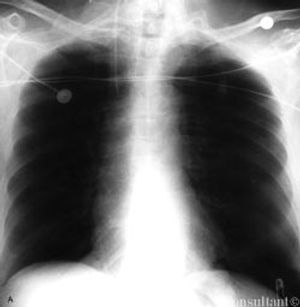

A 67-year-old woman, who had hypertension and chronic obstructive pulmonary disease, presented to the emergency department with mild abdominal discomfort and shortness of breath.